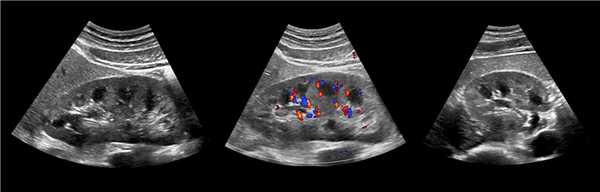

• Серошкальное УЗИ:

о Гомогенное округлое образование, изоэхогенное корковому веществу почки

о Расположена между почечными пирамидами

о Нормальные контуры почки

о Ограничена гиперэхогенной линией соединительной паренхимы и гиперэхогенным треугольным дефектом соединительной паренхимы

о Вдается в почечную пазуху с латеральной стороны

о Гиперэхогенность может быть обусловлена анизотропией

• Цветовая допплерография:

о Нормальная перфузия указывает на неизмененную почечную ткань

о Отсутствует деформация сосудов с нормальными дугообразными артериями, окружающими пирамиды

о Отсутствуют аномальные сосуды

(Левый) На рисунке показана бертиниева колонна, которая является не истинным новообразованием, а разрастанием коркового вещества почки между пирамидами.

(Правый) На продольном ультразвуковом срезе правой почки визуализируется гипертрофированная колонна Бертена, вдающаяся в клетчатку почечной пазухи в среднем отделе почки. Обратите внимание на ее изоэхогенность корковому веществу и гладкие наружные контуры.

(Левый) Продольный ультразвуковой срез правой почки, визуализируется гипертрофирован ная бертиниева колонна, изоэхогенная корковому веществу почки.

(Правый) МРТ с контрастным усилением у этого же пациента (по поводу другого заболевания почки; не показано), визуализируется очаг такой же интенсивности сигнала, как и корковое вещество почки, сравнимое с гипертрофированной бертиниевой колонной.